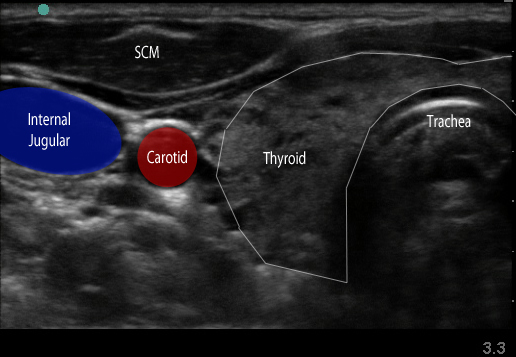

Figure 1. Transverse view over the sternocleidomastoid

- Use a high-frequency 8-12 MHz linear probe and begin scanning transversely over the anterior neck at the level of the cricoid. (Figure 1)

- Probe indicator oriented to operator’s left.

- Depth should be set between 4-8 cm, depending on the size of the patient’s neck.

- Trachea should be clearly seen as a midline hyperechoic arc.

- Slide the probe laterally to the lateral border of the sternocleidomastoid (SCM) (Figure 1), which is a thin muscle superficial to the carotid and jugular.

- Move the probe inferiorly to identify the anterior scalene muscle deep to the lateral border of the SCM. (Figure 2)

- Triangular muscle that is thicker caudally

- Lateral to the internal jugular vein

- If not apparent, slide the probe in a cranio-caudal direction along the lateral border of the SCM to find it

- Identify the middle scalene muscle posterior to the anterior scalene muscle.

- The interscalene space is between these 2 scalene muscles and contains the brachial plexus

- Visualize the brachial plexus here as a stack of circles with hypoechoic centers

- The plexus will look more echogenic, bundled and honeycombed in the caudal interscalene space